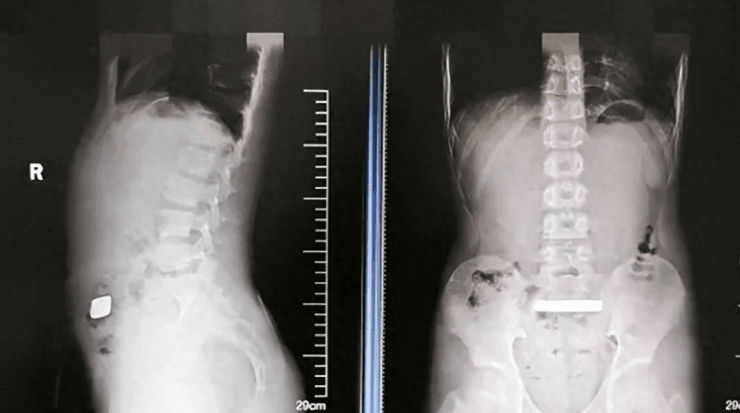

В желудке ребенка нашли золотой слиток | Фото: Jimu News

Родители привезли сына в больницу после того, как он начал жаловаться на вздутие живота. Проведенное рентгенологическое обследование выявило твердый инородный предмет неизвестного происхождения в его пищеварительном тракте.

Врачи сделали рентген

Фото: Jimu News

Терапия не дала желаемых результатов, поэтому через два дня после госпитализации медицинская команда прибегла к хирургическому вмешательству. Повторный рентген подтвердил, что положение слитка оставалось неизменным. Это вызвало опасения относительно возможной перфорации пищеварительного тракта.